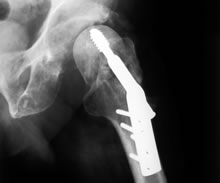

Enter the EU-funded OrthoSim project. Set up to develop an orthopaedic surgery planning tool, OrthoSim has developed a platform that can significantly reduce the risk of post-op complications, as well as provide a means for testing new implant devices, the researchers claim. And in the very near future the platform will provide the base for a new surgical training tool.

Simulating the interface The OrthoSim platform is a system using computer software to create anatomical and implant simulations. The simulation models are based on the work of two leading European biomechanics research centres.

These models were combined to provide a reliable simulation of the interface between the artificial implant and the living tissue, providing surgeons with vital pre-op information.

“Initially we had a model just for lumbar spine implants, but in the last months we have almost completed a validated model for hip implants,” says Lafuente. “We believe that once we finish perfecting a model for knee implants we will have a very strong set of tools to offer surgeons.”